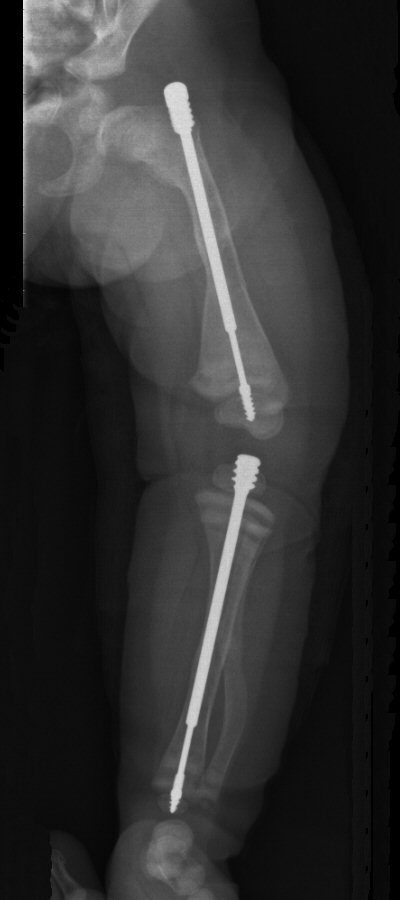

- Använd i första hand märgspikning med god upplinjering

- Profylaktisk märgspikning av långa rörben

Barn med osteogenesis imperfecta vid 6 månader, 2 år resp. 7 år